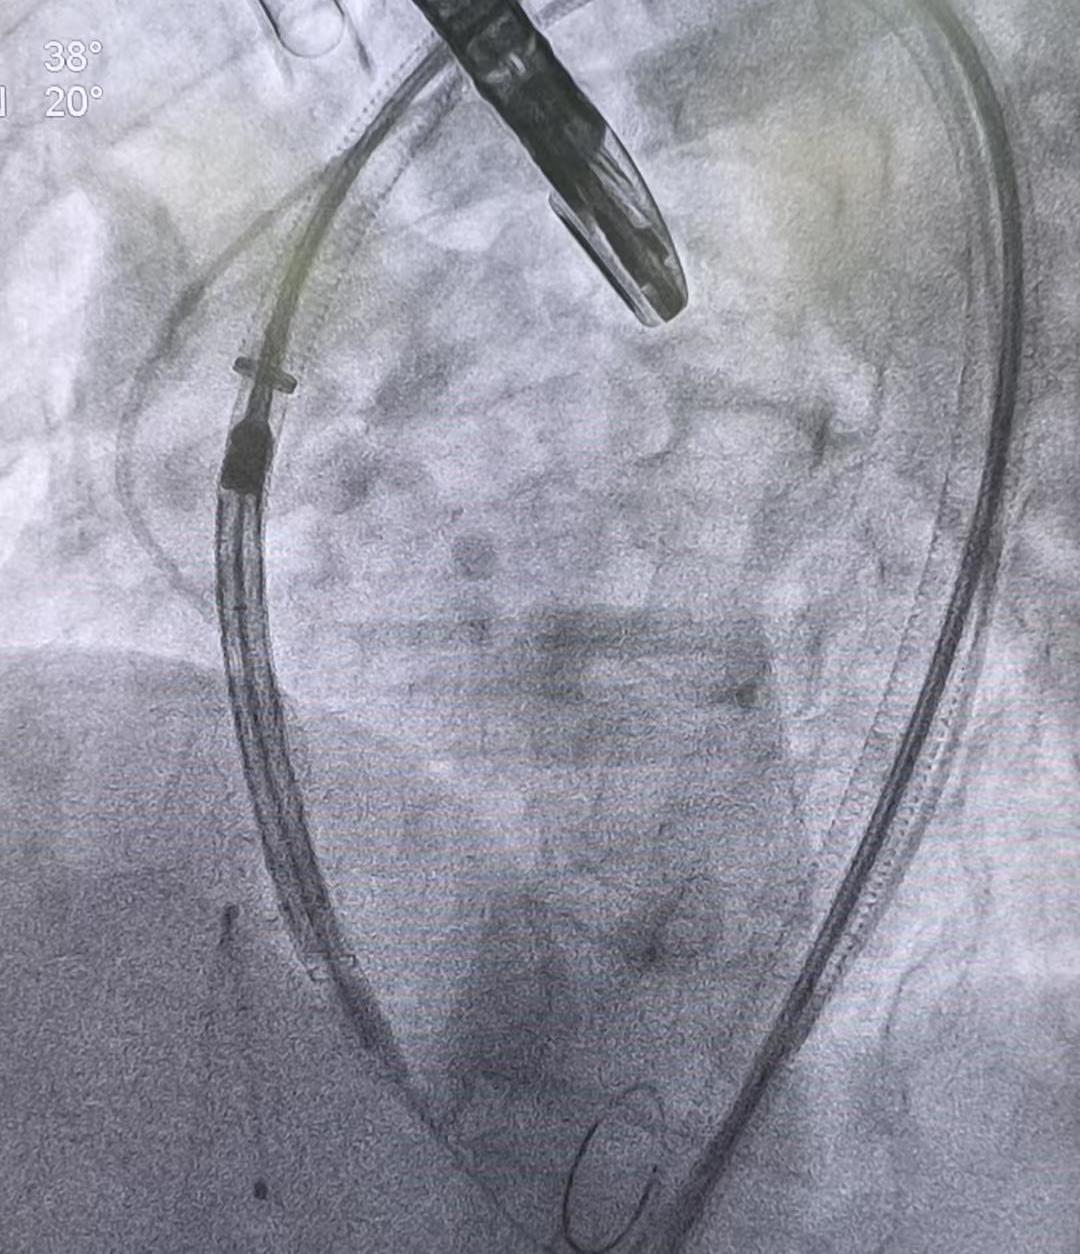

器械创新点分析

本例手术能够突破重重困难取得成功,很大程度上归功于首次临床应用的这款创新导引器械——“跨弓大鞘”导引系统。从其包装参数可以看出,这款导引鞘直径为22F(法国外径单位,约7.3毫米),有效工作长度 70厘米,并具有约180°的固定弯曲形态。如此设计使其既具备足够的内腔直径容纳TAVR输送系统,又拥有足够 长度从股动脉入口一直跨越到达升主动脉。更重要的是,跨弓大鞘预先成型的弧度恰好贴合主动脉弓的解剖走 向,能够在复杂迂曲的动脉路径中建立起一条相对笔直且稳定的通路。

如上图所示,跨弓大鞘在体外呈现出固定的弯曲形态,这一结构设计带来了两大显著优势。首先,它大幅提升了输送系统的同轴性。导引鞘在主动脉弓内形成稳定支撑,使得瓣膜输送导管的前端能够与主动脉瓣口保持中 心轴线的重合,就仿佛在心脏内部铺设了一条笔直的“轨道”,引导瓣膜精确通过主动脉瓣口并对准瓣环位 置。这正是过去复杂TAVR手术中常借助圈套器(Snare)技术所试图达到的效果:通过牵引来矫正人工瓣膜的 不对轴,使瓣膜能够顺利通过瓣口1 。有了跨弓大鞘提供的天然同轴导向,术中无需额外辅助手段也能使输 送系统对准良好,操作更加简洁高效。其次,该鞘管有效抵消了瓣膜递送过程中向上的反作用力,防止装置发生“上跳”移位。在释放瓣膜的关键阶段,粗大的输送系统向心脏推进时往往产生显著的反冲力,而弧形导引 鞘稳稳地支撑在主动脉弓内壁,相当于帮助手术者“顶住”了这股反作用力,避免了人工瓣膜因受力不均而弹出移位。正是凭借这两大创新设计,本例中人工瓣膜才能在缺乏钙化锚定的光滑瓣环中依然被准确固定,未发生位置偏移。